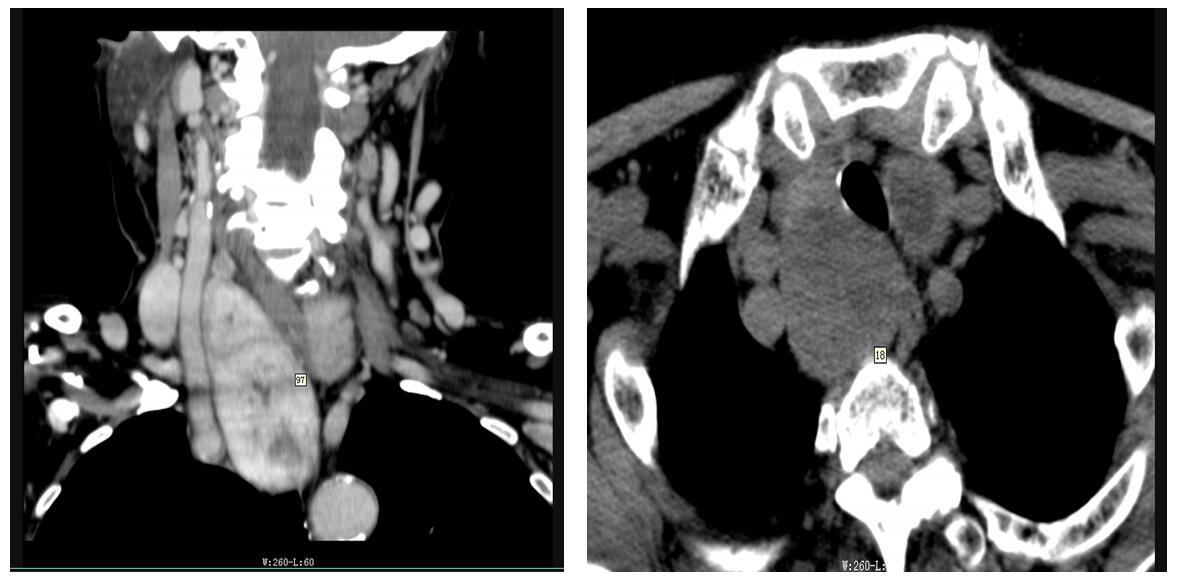

年过7旬的烟台市民老于半年前就出现了胸闷憋气的症状,吞咽也有所不适。近期,他到烟台山医院就诊,在接受彩超检查时发现:他的左侧甲状腺结节为5*4cm,右侧甲状腺结节深入胸骨后,为8*10cm。甲状腺外科诊断老于患上了胸骨后甲状腺肿瘤。近日,他在烟台山医院接受了低领切除术,肿瘤成功切除。现已痊愈出院。

胸骨后甲状腺肿瘤通常是由颈部甲状腺肿瘤向胸骨后突入生长而形成。由于胸骨后组织疏松,甲状腺下极增大或出现病变时,很容易进人胸骨后。生长至一定体积时可压迫气管甚至食管,引起呼吸或吞咽困难。